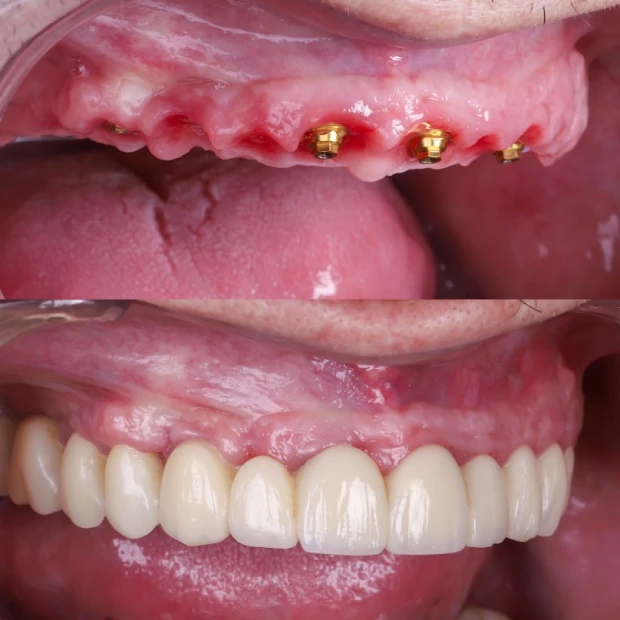

El número de implantes cigomáticos necesarios suele variar entre 1 y 4 por arcada y depende principalmente de la calidad del hueso maxilar y la calidad del hueso cigomático (pómulo). Cuando el hueso del maxilar no es suficiente, utilizamos el hueso cigomático (el pómulo) como punto de anclaje.

Si la pérdida ósea solo afecta a una parte del maxilar, es posible colocar un solo implante cigomático en la zona con peor hueso y completar el resto de la sujeción con implantes tradicionales, que es una cirugía más sencilla y más económica.

Permiten colocar dientes fijos en 24 horas mediante la técnica carga inmediata.

Estética inmediata gracias a la prótesis provisional realizada por nuestro laboratorio en exclusiva.

Antes y después